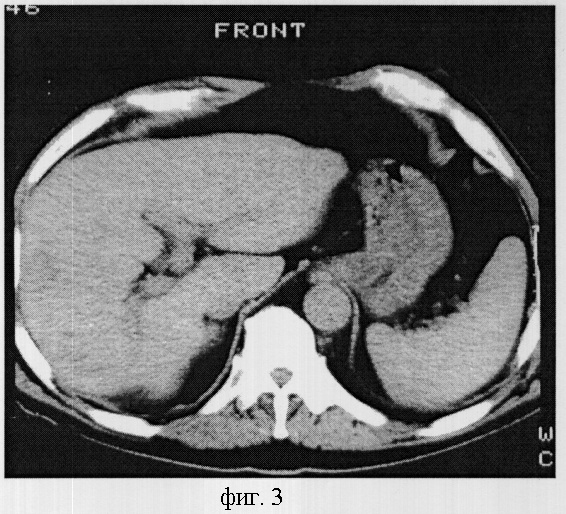

Пример 3. Гипоплазия 1 степени.

Больной Брахнов В.И. 70 лет, проходил обследование по поводу кисты левой почки. При компьютерно-томографическом исследовании печень расположена нормопетально, поверхность печени гладкая, край левой доли закруглен, а задняя поверхность правой доли умеренно деформирована. Структура паренхимы однородная, плотность 70 HU. Общий объем печени составил 1330,0 см3. При этом объем правой доли был меньше обычного и составлял 516,9 см3. Изменение объема правой доли обусловлено уменьшением объема 6 и 7 сегментов, объем которых равнялся 87,1 и 85,3 см3, соответственно, а коэффициент К=0,36 и 0,35, что соответствовало гипоплазии 1 степени. Форма сегмента сохранена, а диаметр сегментарных ветвей шестого и седьмого сегментов изменен незначительно и был равен 0,5 см (фиг.3).